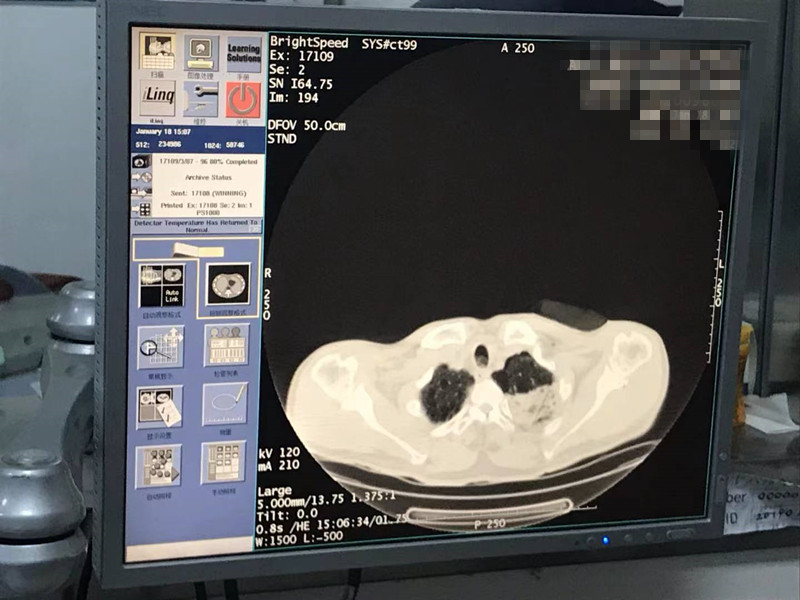

2021年1月份肺部氩氦刀手术